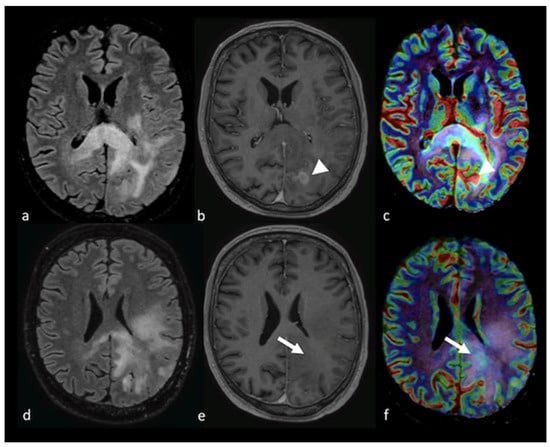

3.3.1. Dynamic Susceptibility Contrast-Enhanced Perfusion

- Halshtok Neiman, O.; Sadetzki, S.; Chetrit, A.; Raskin, S.; Yaniv, G.; Hoffmann, C. Perfusion-weighted imaging of peritumoral edema can aid in the differential diagnosis of glioblastoma mulltiforme versus brain metastasis. Isr. Med. Assoc. J. 2013, 15, 103–105. [Google Scholar] [PubMed]

- Neska-Matuszewska, M.; Bladowska, J.; Sasiadek, M.; Zimny, A. Differentiation of glioblastoma multiforme, metastases and primary central nervous system lymphomas using multiparametric perfusion and diffusion MR imaging of a tumor core and a peritumoral zone-Searching for a practical approach. PLoS ONE 2018, 13, e0191341. [Google Scholar] [CrossRef]

- Askaner, K.; Rydelius, A.; Engelholm, S.; Knutsson, L.; Latt, J.; Abul-Kasim, K.; Sundgren, P.C. Differentiation between glioblastomas and brain metastases and regarding their primary site of malignancy using dynamic susceptibility contrast MRI at 3T. J. Neuroradiol. 2019, 46, 367–372. [Google Scholar] [CrossRef]

- Blasel, S.; Jurcoane, A.; Franz, K.; Morawe, G.; Pellikan, S.; Hattingen, E. Elevated peritumoural rCBV values as a mean to differentiate metastases from high-grade gliomas. Acta Neurochir. 2010, 152, 1893–1899. [Google Scholar] [CrossRef] [PubMed]

- Lin, L.; Xue, Y.; Duan, Q.; Sun, B.; Lin, H.; Huang, X.; Chen, X. The role of cerebral blood flow gradient in peritumoral edema for differentiation of glioblastomas from solitary metastatic lesions. Oncotarget 2016, 7, 69051–69059. [Google Scholar] [CrossRef] [PubMed]